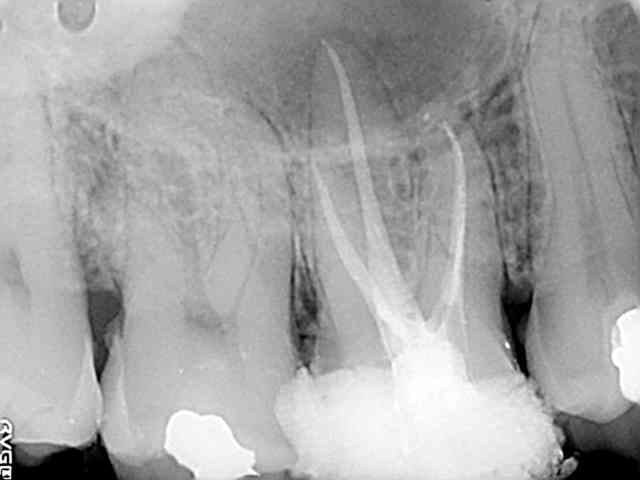

...avec même une petite touche égyptienne sur la première qui aurait fait plaisir à qui vous savez.

Une petite de ce matin et une plus ancienne, toutes les deux avec la même "recette".

Vous remarquerez en zoomant sur celle de ce matin comme le matériau a bien "squirté" en mésial. Devant de tels résultats, je ne vois pas pourquoi j'irai m'emmerder avec un system B...